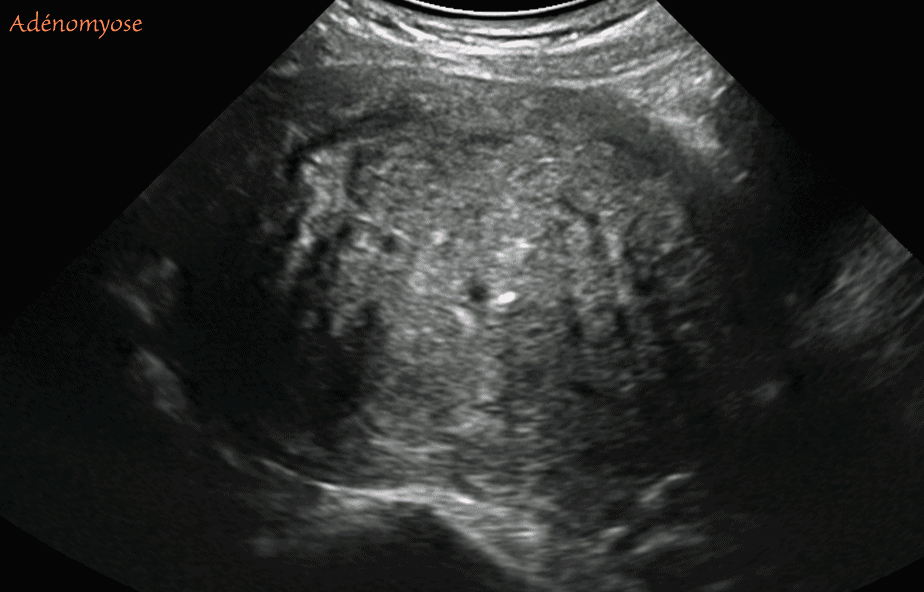

Utérus - Adénomyose florissante - images échographiques

Images montrant l'un des aspects échographiques de l'adénomyose